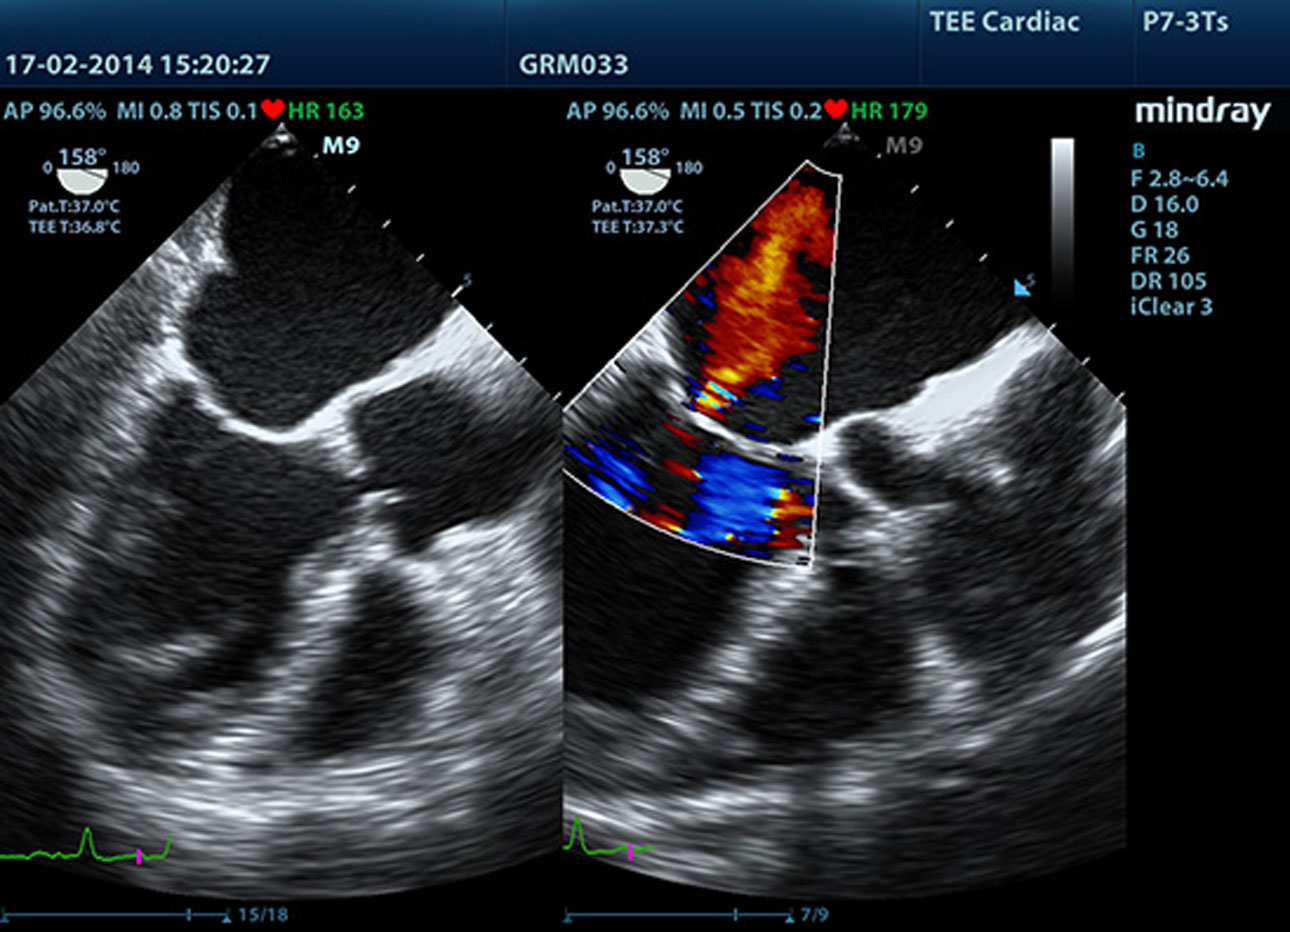

P7-3Ts_MR_Dual 2D Color

• p53-s5-5-web